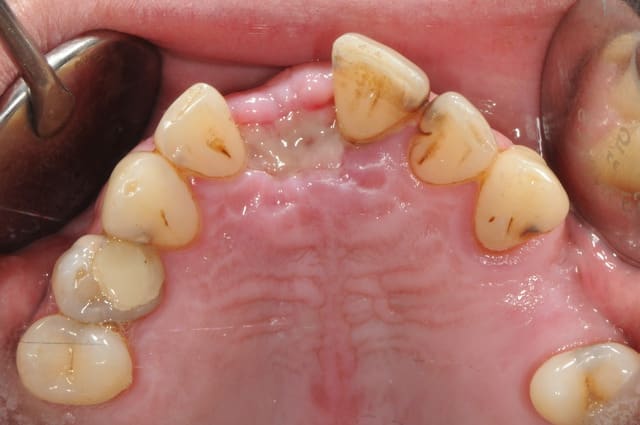

Dans le cas présenté, les images sont sur-exposées, couleur fade.

Need better white balance on your picture.

Set your camera white balance to flash, and reduce your flash output.

Avec un parodonte épais comme celui-ci, former la gencive n'est pas trop difficile.

With a gum biotype like this on, manipulating the gum is not very difficult.

Il y a aussi un gummy-smile et un sourire inversé, dommage après tant de couronnes.

The final result is a gummy smile with reverse smile line...too bad after all those crowns. A simple perio surgery could have give better result.